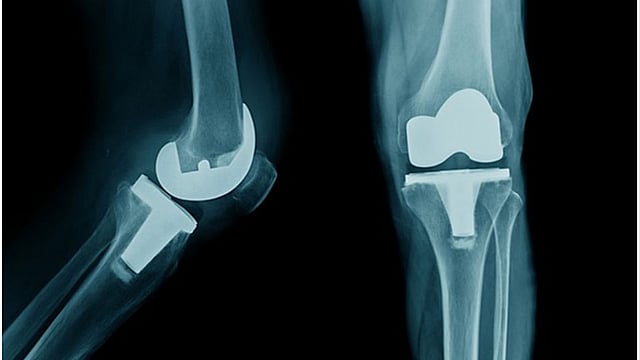

दोन्ही गुडघा बदलीच्या शस्त्रक्रियेनंतर ६३ वर्षांच्या महिलेने ३,५०० किलोमीटर नर्मदा परिक्रमा पायी पूर्ण केली.

पुणे - दोन्ही गुडघा बदलीच्या शस्त्रक्रियेनंतर (Knee Surgery) ६३ वर्षांच्या महिलेने (Women) ३,५०० किलोमीटर नर्मदा परिक्रमा पायी (Walking) पूर्ण केली. पुण्यातील साईश्री हॉस्पिटलमध्ये त्यांच्यावर शस्त्रक्रिया झाली होती. (63 Year Old Woman Walks 3500 Kilometers after Knee Replacement)

सुलभा कुलकर्णी या २००९ पासून गुडघेदुखीने त्रस्त होत्या. दैनंदिन जीवनातील कामे करताना त्यांना त्रास होत होता. डॉक्टरांनी त्यांना गुडघाबदलीची शस्त्रक्रिया सांगितली होती; परंतु सरकारी कर्मचारी असल्याने आणि घरगुती कामामुळे त्या शस्त्रक्रिया करण्यासाठी मानसिकदृष्ट्या तयार नव्हत्या. २०१५ मध्ये जेव्हा त्या सेवानिवृत्त झाल्या, तेव्हा त्यांना गुडघेदुखीचा त्रास जाणवू लागला. म्हणून त्यांनी गुडघाबदलीची शस्त्रक्रिया करण्याचा निर्णय घेतला. साईश्री हॉस्पिटल येथे रोबोटिक जॉइंट रिप्लेसमेंट सर्जन डॉ. नीरज आडकर यांच्या नेतृत्वात कुलकर्णी यांच्यावर शस्त्रक्रिया केली.

नवीन तंत्रज्ञानामुळे शस्त्रक्रियेच्या पद्धतीमध्ये प्रगती झाल्यामुळे रुग्णाला हॉस्पिटलमध्ये कमी वेळ राहावे लागते; तसेच कमी वेळेमध्ये सांध्यांची चांगली हालचाल करता येते. ज्यांना असे वाटते, की शस्त्रक्रियेनंतर आपले आयुष्य संपले, त्यांच्यासाठी सुलभा कुलकर्णी प्रेरणा आहेत.